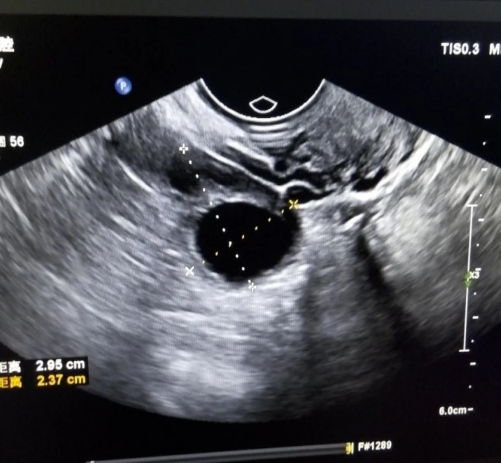

B超显示子宫内膜厚度只达到7.6mm可以移植胚胎吗?

做试管婴儿的姐妹最纠结的就是内膜厚度。最近有患者检查发现内膜只有7.6mm,比常见的8mm标准薄了0.4mm,急得直问:〝我这内膜是不是没救了?还能不能移植?〞其实这个问题就像问〝鸡蛋壳薄了0.1毫米能不能孵出小鸡〞,答案不能只看一个数字。一、厚度达标线真的是铁门槛吗?教科书上说8-14mm是理想厚度,但临床发现:1. 7.6mm成功怀孕的案例真实存在(文献记载最低6.7mm也有活产)2. 就像同